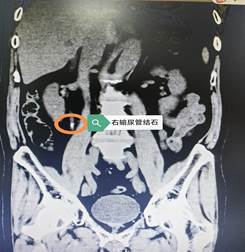

当天,这位韩国患者因突发右下腹疼痛,紧急来到院泌尿外科求诊。经检查,确诊为右侧输尿管结石并伴有肾绞痛。考虑到患者病情紧急且身在异国,语言不通、环境陌生,泌尿外科立即启动应急响应机制。

为尽快解除患者痛苦,在完善相关术前检查后,泌尿外科团队与手术室、麻醉科紧密配合,于入院当晚即为患者实施了“经尿道右侧输尿管镜钬激光碎石取石术+右输尿管支架置入术”。赵永斌主任表示:该手术属于微创治疗,利用人体自然腔道,体表无切口,具有损伤小、出血少、恢复快的显著优势。